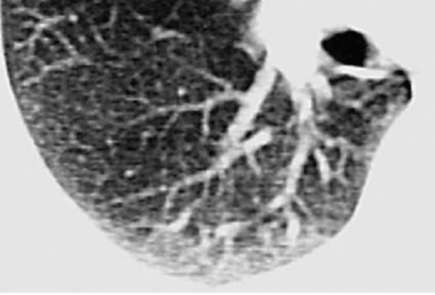

Лучевые методы исследования. Рентгенологическая картина при ЭТА зависит от стадии заболевания. В начальной фазе выявляются признаки отека интерстициальной ткани легких и распространенные мелкоочаговые затенения. При прогрессировании процесса формируются двусторонние изменения легочного рисунка по типу интерстициального фиброза, преимущественно в нижних отделах легких (рис. 2.28). В далеко зашедших случаях определяется мелко- и крупноячеистая деформация легочного рисунка. Описаны случаи, когда единственным рентгенологическим признаком болезни был односторонний плевральный выпот. Отсутствие каких-либо изменений на рентгенограммах отнюдь не исключает ЭТА. Так, при бериллиозе у 23-59% больных может выявляться умеренно выраженная двусторонняя лимфоаденопатия, а в ряде случаев - рентгенотрицательная форма бериллиоза (Dweik R.A., 2015). У 30% из 71 больных ЭТА, наблюдавшихся нами в клинике пульмонологии, в момент обследования изменений на рентгенограммах не было (Орлова Г.П., 2019). Группа больных ЭТА была обозначена условно как рентгенотрицательная группа. Уточнить диагноз помогает КТ легких, выявляющая интерстициальные изменения в легочной ткани по типу «матового стекла», усиление и деформацию легочного и сосудистого рисунка (рис. 2.29), фиброзные изменения тяжистого и звездчатого типов, на поздних стадиях - «сотовое легкое». ВРКТ выявляет «матовое стекло» и другие изменения в легочной паренхиме, которые не видны при обычном рентгенологическом исследовании. Но даже ВРКТ не всегда выявляет изменения в легочной ткани. Так, в 25% случаев гистологически подтвержденного хронического берил-лиоза легких ВРКТ была нормальной (Dweik R.A., 2013; Амосов В.И., Сперанская А.А., 2015; Amanullah S. et al., 2015).

Проведенное нами динамическое исследование КТ-паттернов у 42 больных ЭТА показало трансформацию отдельных типов интерстициальных пневмоний по мере прогрессирования патологического процесса в фиброзную НСИП или ОИП (рис. 2.30), что подтверждает объединительную концепцию интерстициальных пневмоний вне зависимости от этиологического фактора, которые являются не отдельными нозологическими формами, а стадиями течения фиброзирующего процесса в легких (Илькович М.М., Новикова Л.Н., 2018; Орлова Г.П. и др., 2019).